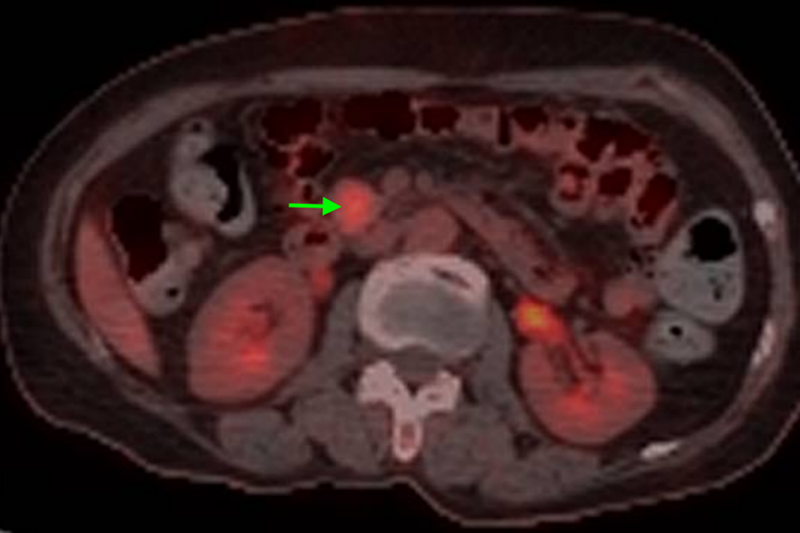

經(jīng)檢查,陳大嬸有低血糖癥狀、代謝性腦病,進(jìn)一步行PET/CT檢查及腹部增強(qiáng)CT檢查后考慮為胰島素瘤。內(nèi)分泌科立即組織肝膽胰外科、神經(jīng)內(nèi)科、內(nèi)分泌科、臨床營養(yǎng)科、麻醉科等多學(xué)科聯(lián)合診療,專家們討論后一致認(rèn)為陳大嬸的胰島素瘤有明確手術(shù)指征,于是轉(zhuǎn)入肝膽胰外科進(jìn)一步手術(shù)治療——腹腔鏡探查、胰腺鉤突腫瘤切除術(shù)。

專家團(tuán)隊(duì)進(jìn)行了精心的術(shù)前準(zhǔn)備,并制定了精細(xì)化麻醉方案。術(shù)中,肝膽胰腺外科手術(shù)團(tuán)隊(duì)參考術(shù)前CT資料及術(shù)中腔鏡超聲精確定位腫瘤,將胰島素瘤完整切除,整個手術(shù)過程時間僅為80分鐘,出血量僅為5ml。術(shù)后,患者血糖水平恢復(fù)到正常水平,認(rèn)知障礙逐步得到改善,一周后復(fù)查CT未見胰漏。出院前,陳大嬸體力、飲食、精神等方面完全恢復(fù)正常,已能和家人順利交流,終于擺脫了被誤解的慘痛經(jīng)歷。